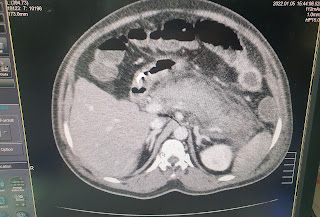

CT ABDOMEN:

Acute pancreatitis with alcohol dependence syndrome